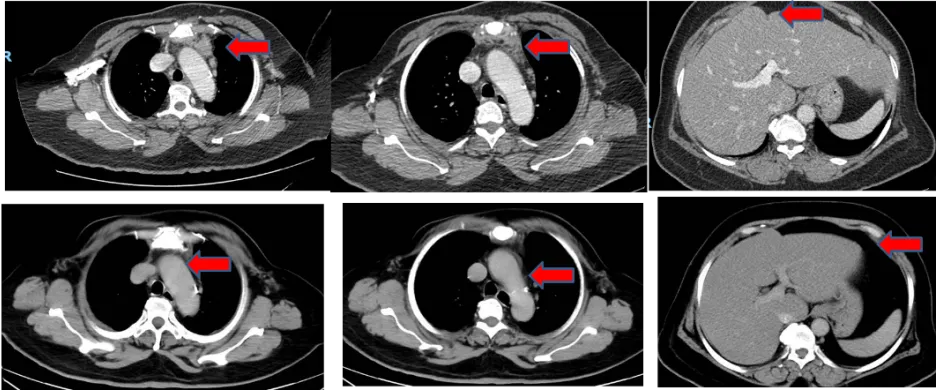

二线治疗

治疗方案:2020年1月,患者病情出现进展,调整为全口服方案:“长春瑞滨软胶囊(140mg po d1、d8)+阿帕替尼(0.25g po qd)”,每3-4周为一周期。

疗效评价:PR

PFS2:59个月

图片3.png

图3 2024年12月 CT结果